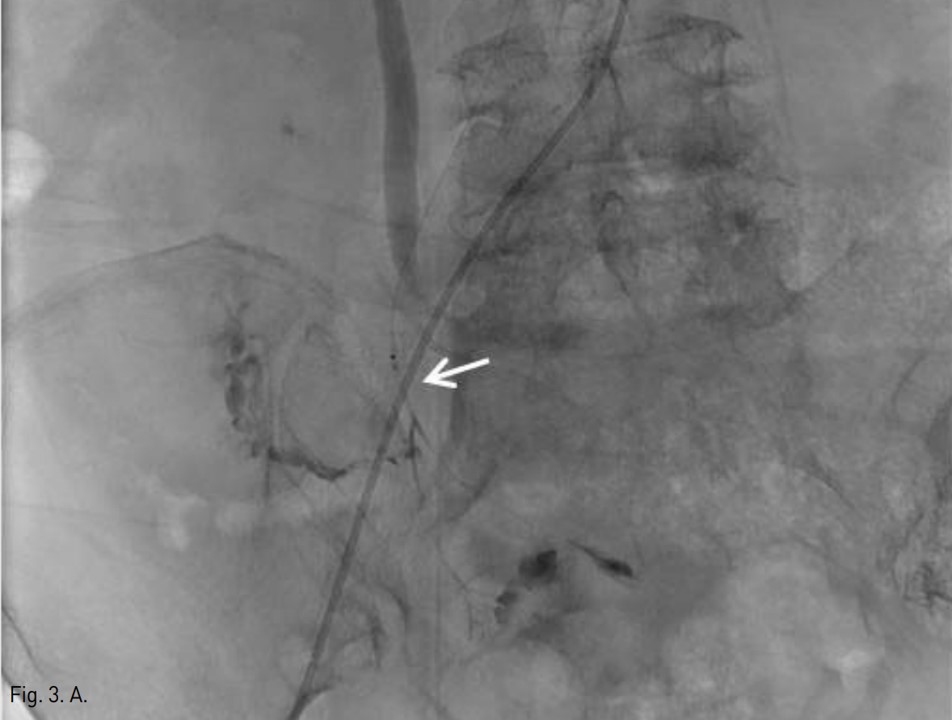

Fig. 3. A

Fig. 3A, B. Ileocolic (A) and right colic (B) arterial branches were embolized by using gelatin sponge, respectively(arrows).